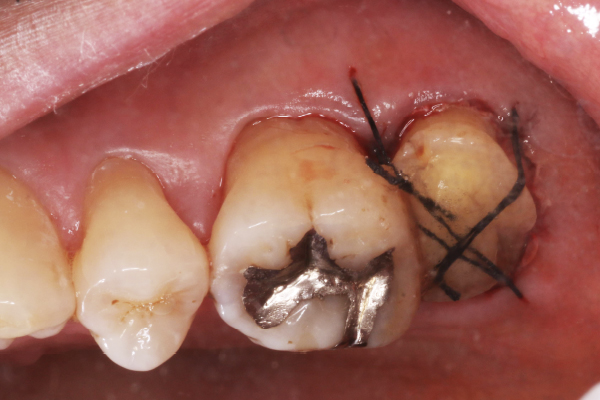

1.初診時口腔内写真

左下の奥歯が痛くて歯科医院を受診したところ、抜歯の診断となりました。何とか残す方法がないか相談したいとのことで来院されました。

2.初診時エックス線写真

左下の1番奥の歯に神経に達する大きなむし歯を認めました。

今回の症例では、むし歯が歯ぐきの中まで深く進行していたため、抜歯と言われてしまったようです。抜歯の適応でもおかしくないむし歯ですが、患者さんは歯の保存を強く希望されました。

3.むし歯除去、歯肉切除

まずは、抜髄·根管充填を行ないました。

本症例は歯ぐきの下まで進行しているむし歯なので、症例4、12のように歯冠長延長術(クラウンレングスニング)を行うことも可能でした。

しかし、下顎最後方臼歯の歯肉は厚みがあるため、手術を行なっても歯肉を下げきれないことがあります。

今回は、電気メスで少し歯肉切除し、歯型を取って土台をたてる方法(間接法支台築造)を選択いたしました。